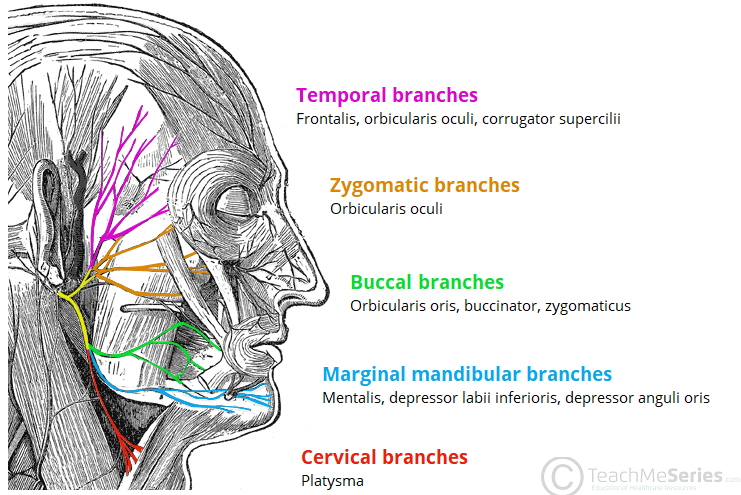

CN VII

Parotid plexus(支配表情肌)

- Temporal br.

- Zygomatic br.

- Buccal br.

- Marginal mandibular br.

- Cervical br.